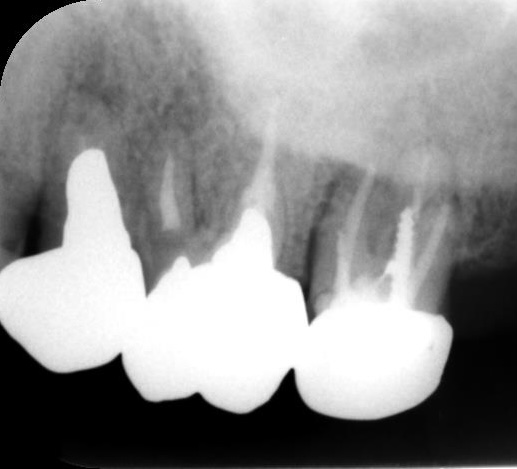

銀歯・詰め物をした歯に痛みがあり来院

年代/性別 40代/女性 主訴 他院で一年半前に治療した歯(銀歯を入れた歯)が痛い 治療方法 感染根管処置 費用 診断費用:¥16,500

感染根管治療:¥154,000

リトリートメント:¥44,000

ファイバーコア:¥38,500

オールセラミックスクラウン:¥187,000備考(デメリット) 経過観察が必要

右下の奥から2番目の歯が痛いという主訴で来院されました。過去に虫歯治療をしており、詰め物(銀歯)が入っている歯でした。

CTを撮影し確認してみると、近心に根尖病変があり、歯髄の生活反応も無かったので、感染根管処置が必要という診断になりました。

治療の流れとしては、 ①感染根管治療 ②仮歯を入れて6ヶ月経過観察 ③最終の被せ物の装着 といった感じになります。

感染根管治療をした後は、必ず仮歯を入れて6ヶ月経過観察を行います。 -

6ヶ月の経過観察が終了し、最終の被せ物を入れました。

仮歯(プロビジョナルレストレーション)は最終の被せ物を入れる前に必要な準備段階であり、噛み合わせや、頬や舌を噛みやすい形態になっていないかの確認・骨の再生の経過観察など多くの目的があります。仮歯は削ったり盛り足したりして調整可能ですが、最終の被せ物はセラミックスで出来ている為、大きな修正ができません。

約6ヶ月の経過観察を通じて適合を整えてから最終の被せ物を作ることが、後々のトラブル防止につながります。 -

根尖病変が無くなり、透過像が消失しているのが確認出来ます。

当院では、歯肉や歯槽骨の状態、被せ物の形態を完璧に整えてから最終の被せ物を装着するため、治療後も問題が起きにくく、長く快適にご使用いただけます。